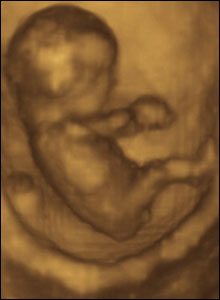

Eight weeks gestation, 40mm from crown to rump.

1 of 10

At eight weeks gestation, this foetus is able to kick and straighten his legs, turn them round and move his arms up and down.